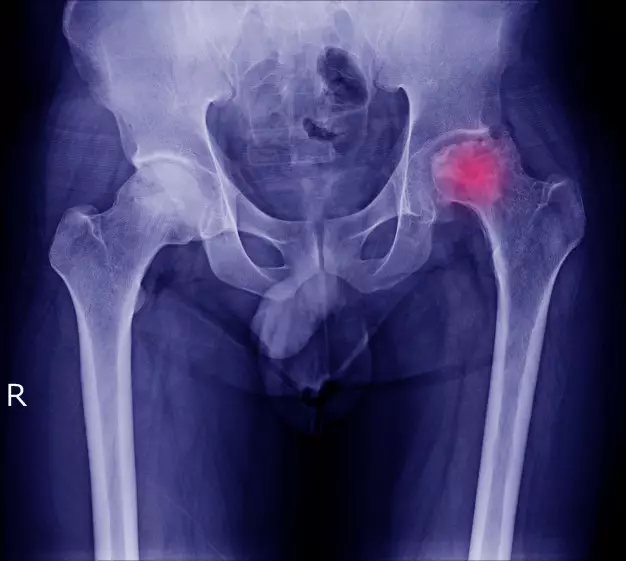

1. Nyeri tulang.

foto: freepik.com

Kanker prostat biasanya diawali dengan nyeri tulang belakang dan tulang paha. Selain itu gejala mula kanker prostat juga diawali dengan nyeri di tulang rusuk. Jika kanker menyebar ke tulang belakang, bisa terjadi pelemahan pada kaki.